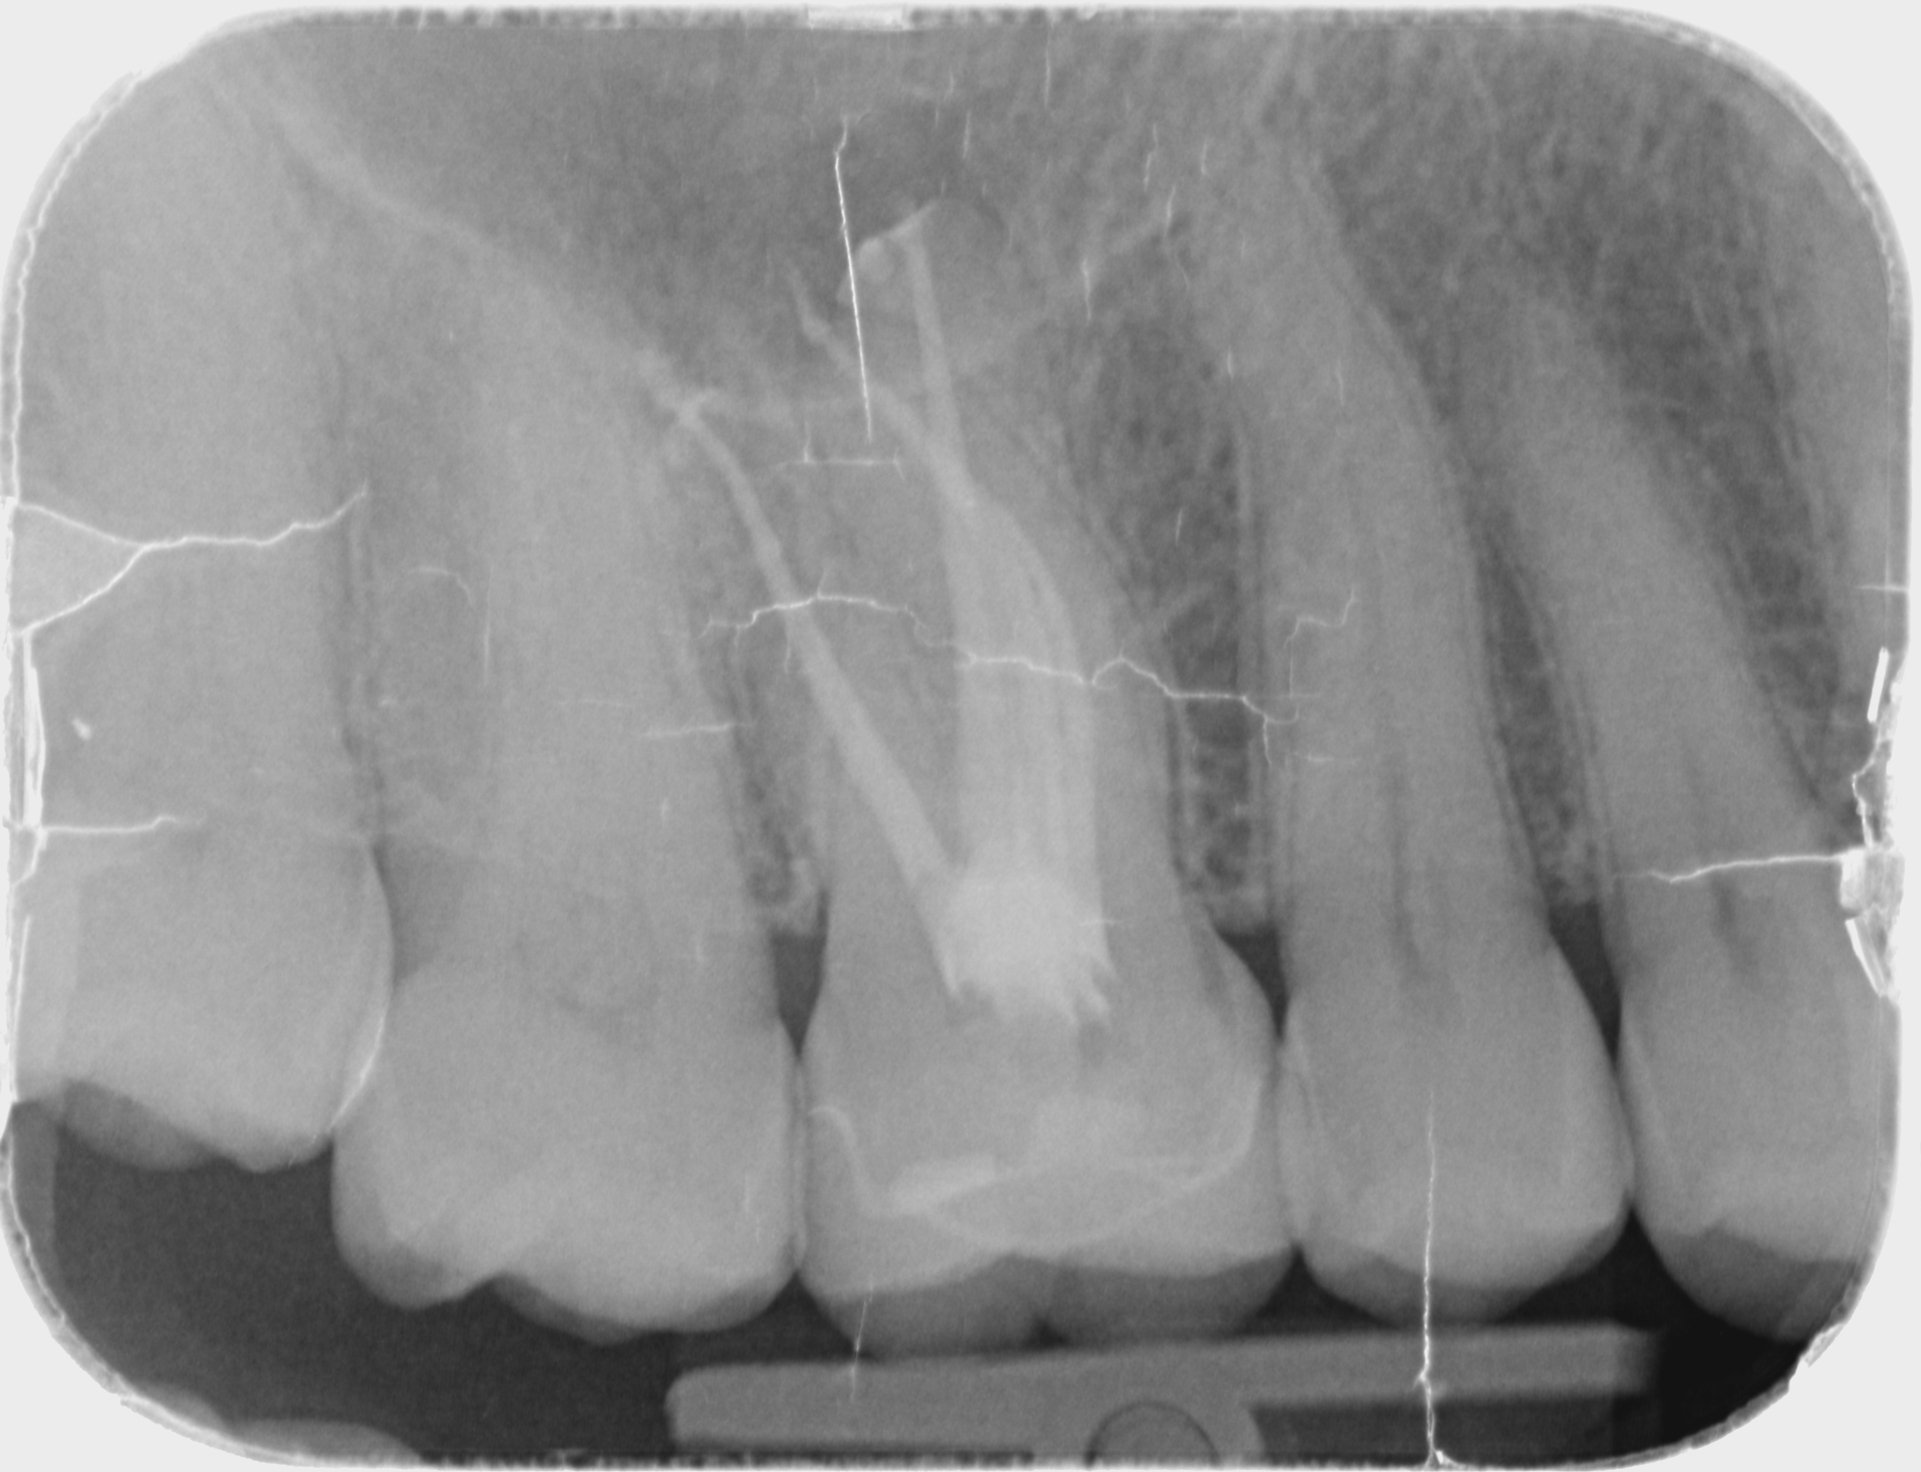

Patient presented with pain on 16. PA radiograph shows PARL.

Post operative radiograph showing joining on MB1 and MB2 canal at apical 1/3.